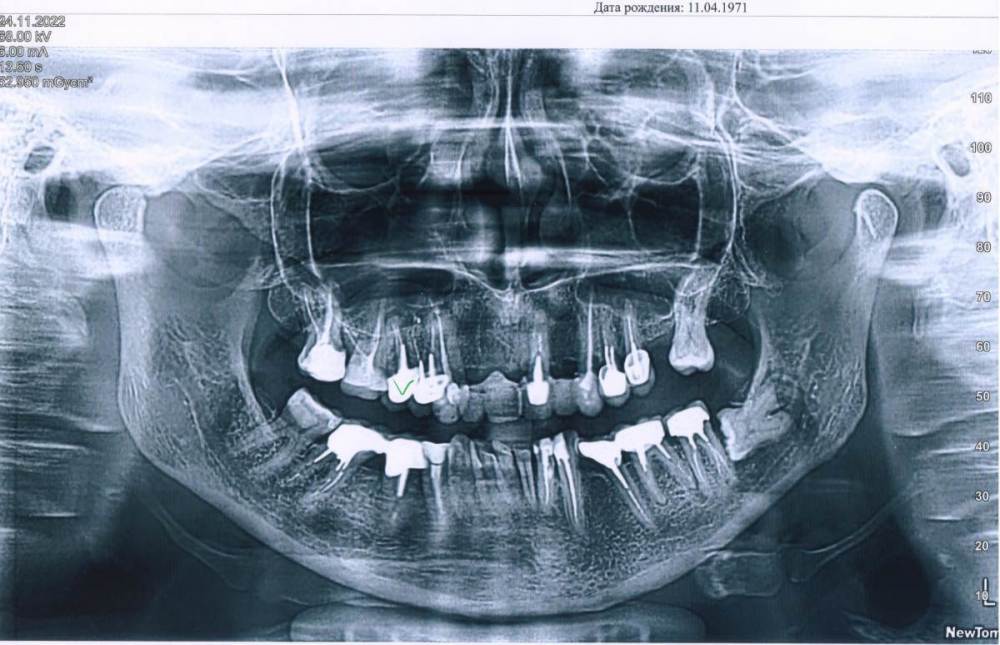

Svettala Опубликовано 25 ноября, 2022 Поделиться Опубликовано 25 ноября, 2022 Добрый день, уважаемые стоматологи. Пятерка справа под коронкой лет 15. Не беспокоит, но изредка появляется ощущение не боли, а какого-то просто неприятного момента. Периодически делала снимки и то, что на нем киста слышала лет 10. То есть она давно. По снимку КТ она 4.3 мм. Сейчас хотелось бы просто заменить коронки и врач предлагаете либо лечить (но без гарантированного результата длительное время) или удалить и поставить имплант. КТ загрузить не могу пока, но есть панорамный снимок. Ваше мнение - удалить нельзя лечить-где поставить запятую))) ? Ссылка на комментарий

chervoncevdaniil Опубликовано 26 ноября, 2022 Поделиться Опубликовано 26 ноября, 2022 (изменено) В данном зубе установлена литая культевая вкладка. Часто достать ее для перелечиваания достаточно проблемно,а если даже и удается,то вопрос чтто останется в таком случае от зуба,чтобы потом его заново запротезировать надолго. Если хотите попытатьтся,то нужно чтобы терапевт попробовал ее извлечь и показал ортопеду что при эттом остается от зуба. Если оставшихся тканей и толщины стенок достаточно по мнению ваашего ортопела,то тогда пробоваать перелечить. Если нет(что скорее всего)-удаление и имплантация,поттому что еще ведь нужно качественно перелечить Изменено 26 ноября, 2022 пользователем chervoncevdaniil 2 2 Ссылка на комментарий